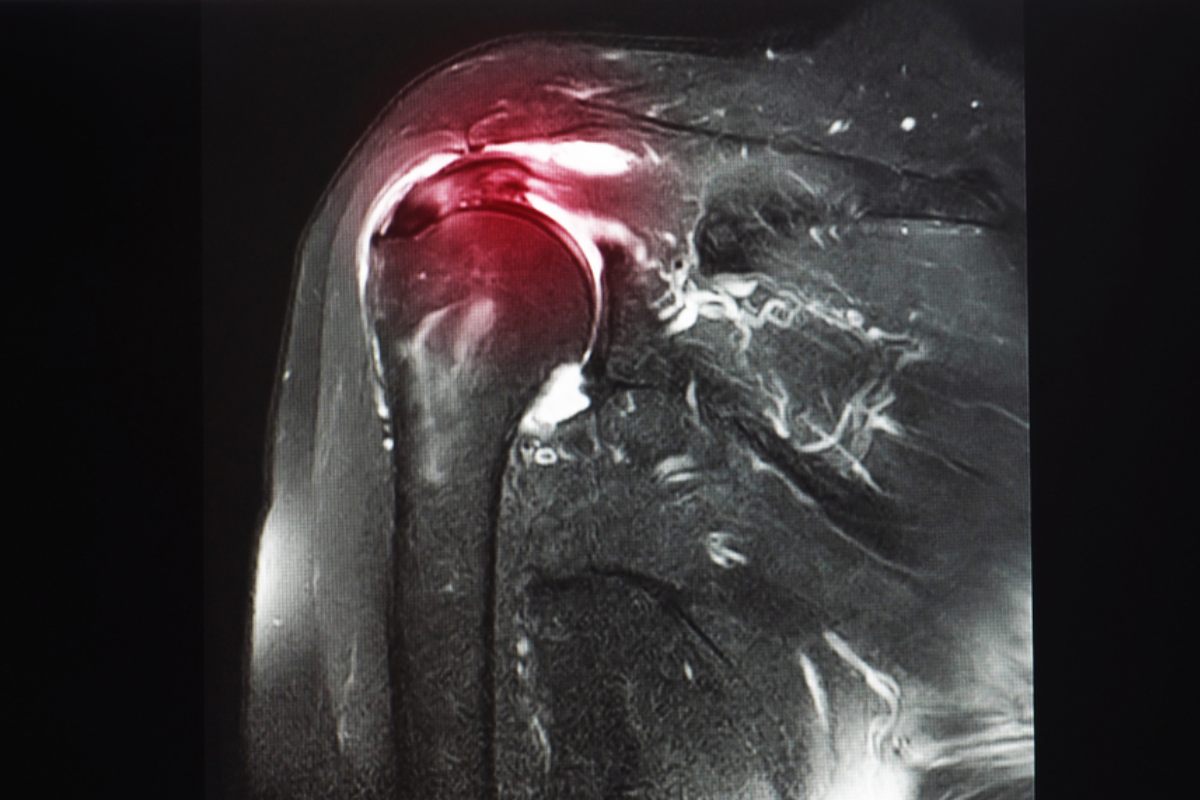

2. تصویربرداری

- MRI (تصویربرداری رزونانس مغناطیسی): بهترین روش برای دیدن پارگی تاندون و میزان آسیب عضله.

- اولتراسوند (سونوگرافی): برای ارزیابی پارگیهای ناقص و وضعیت تاندونها مفید است و قابلیت بررسی حرکتی شانه را هم دارد.

- X-ray: برای بررسی استخوان، اسپور استخوانی یا سایر تغییرات ساختاری شانه استفاده میشود، اگرچه پارگی تاندون را بهطور مستقیم نشان نمیدهد.

ترکیب معاینه بالینی و تصویربرداری باعث میشود تشخیص دقیقتر باشد و از اشتباهات رایج، مثل نسبت دادن درد شانه یا علت درد بین دو کتف به مشکلات دیگر، جلوگیری شود.